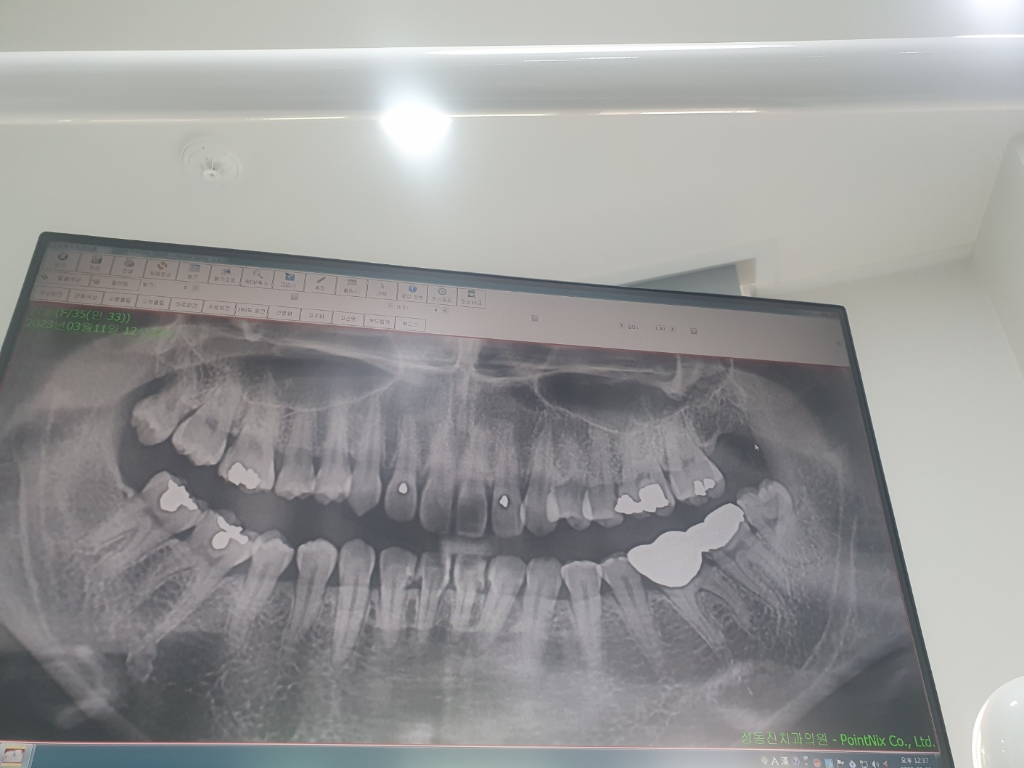

위사진은 작년파노라마 사진입니다..

엑스레이 상으로 보면 잇몸이 크게 안좋거나 그렇진 않아 보이는데 피가 나는건 아래 사랑니쪽에 염증이 생겨서 그럴 가능성이 높아 보입니다.

작년 파노라마 사진상으로만 봐서는 잇몸뼈가 많이 녹거나 한 상태는 아닙니다. 다만, 현재 상태는 알기 어렵고 잇몸 출혈 증상으로 봐서는 치은염의 단계로 보입니다. 치은염에서 잘 관리를 해줘야 잇몸뼈가 녹는 치주염 단계로 진행되지 않습니다.

치주염이 있을 가능성이 높으며 작년사진으로는 크게 문제는 안됩니다. 잇몸치료가 도움이 될 수 있으며 양치를 계속 잘해줘야 합니다.